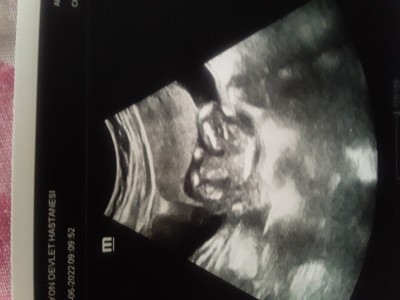

Fotografi anlayan varmi neresi bu bebegin hicbir fikrim yok bakiyorum bakiyorum anlamiyorum doktor hic kontrol etmeden kiz dedi elime bunu verdi gonderdi yardimm

Gebelik haftası 14+6

bu resim bebegin alttan cekilmis poposunun fotosu canım bacak arası boş olduğu için de kız diyebilmis direk dikkatli bakarsan at nalı seklinde bacakları belli ve özel bölgesi cekilmis hayırlı olsun